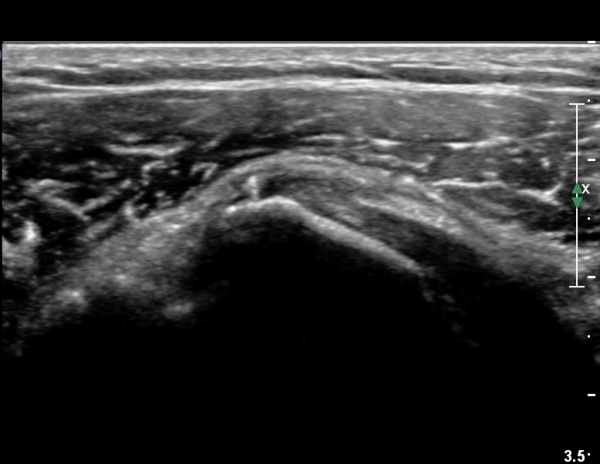

ÃÊÀ½ÆÄ ¼Ò°ß :  È¸Àü±Ù°³°£°Ý(rotato cuff interval) ³»Ãø °Ë»ç»ó  »óºÎ °ß°©Çϱٰǿ¡ ƯÀÌ ¼Ò°ß º¸ÀÌÁö ¾ÊÀ½(»çÁø 1).

°ß°©ÇϱٰǠ Á¾´Ü¸é°Ë»ç¿¡¼­ °ÇºÎÂøºÎ¿¡ ÀÛÀº ¼®È¸È­À½¿µÀÌ °üÂûµÊ(»çÁø 2).